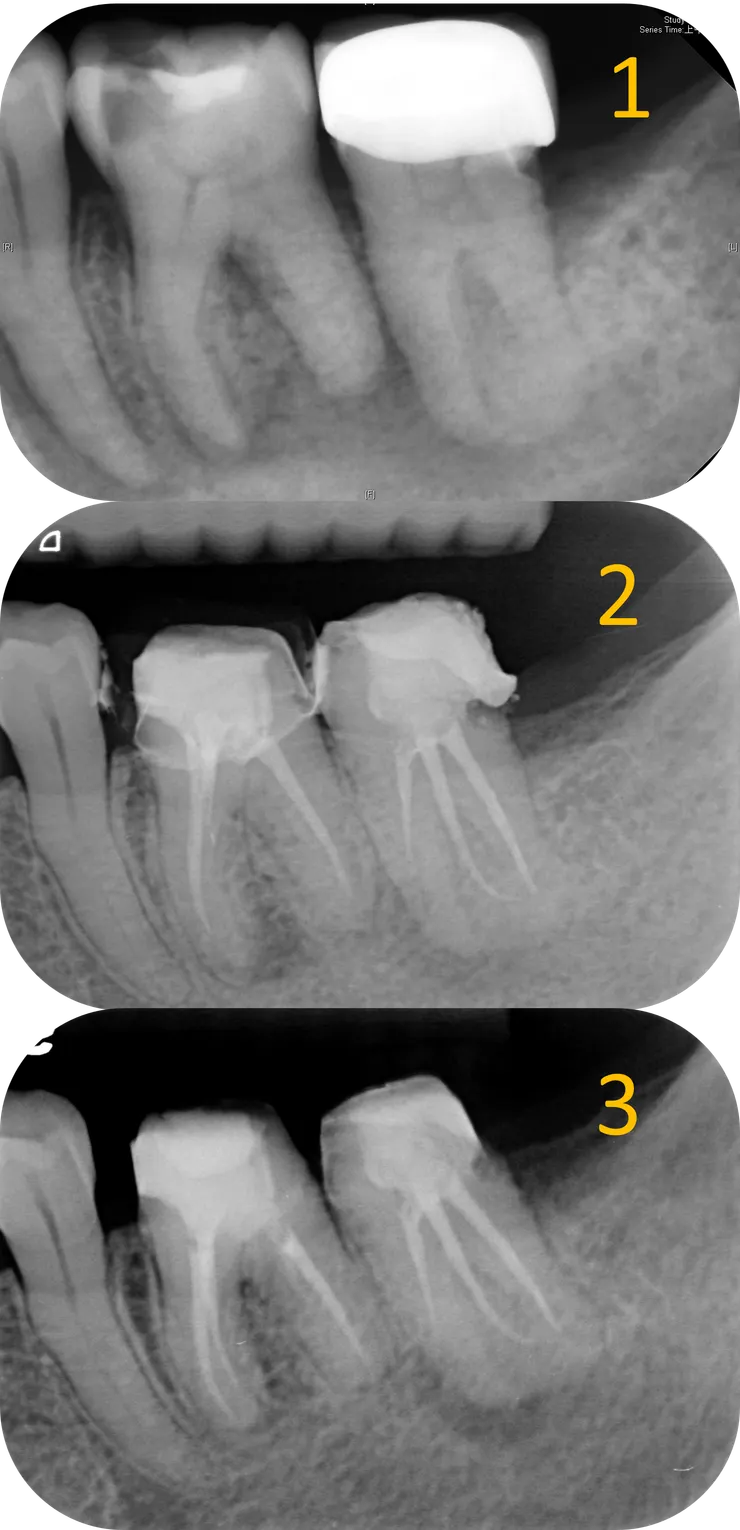

1. 從 initial PA 可以看得出來 36 & 37 的 canal 都細小鈣化到看不到。

2. 第一位 endo 專完成了將近 5 個 canal 後,36 distal apical lesion 有了明顯的癒合。

3. 我接手後完成了 36 的 retreat, mesial apical lesion 也顯著癒合。

1. Initial.

2. 第一次 RCF 後過了六年,36 distal apical lesion 顯著 healing.

3. 我接手後,歷經一年九個月,12 個 appointment 的治療,完成了這兩顆的 retreatment.

4. 一年後的追蹤,36 & 37 的 apical lesion 皆顯著癒合。